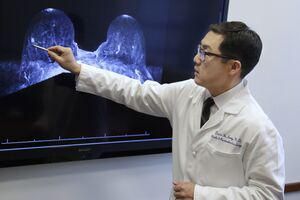

Șansă în plus pentru pacienții diagnosticați cu tumori cerebrale sau Parkinson. Un celebru neurochirurg va oferi consultații gratuite

În data de 26 ianuarie 2019, prof. univ. dr. Serdar Baki ALBAYRAK, unul dintre cei mai cunoscuti neurochirurgi din Turcia, revine la Constanţa, pentru a… Citește mai mult »Șansă în plus pentru pacienții diagnosticați cu tumori cerebrale sau Parkinson. Un celebru neurochirurg va oferi consultații gratuite